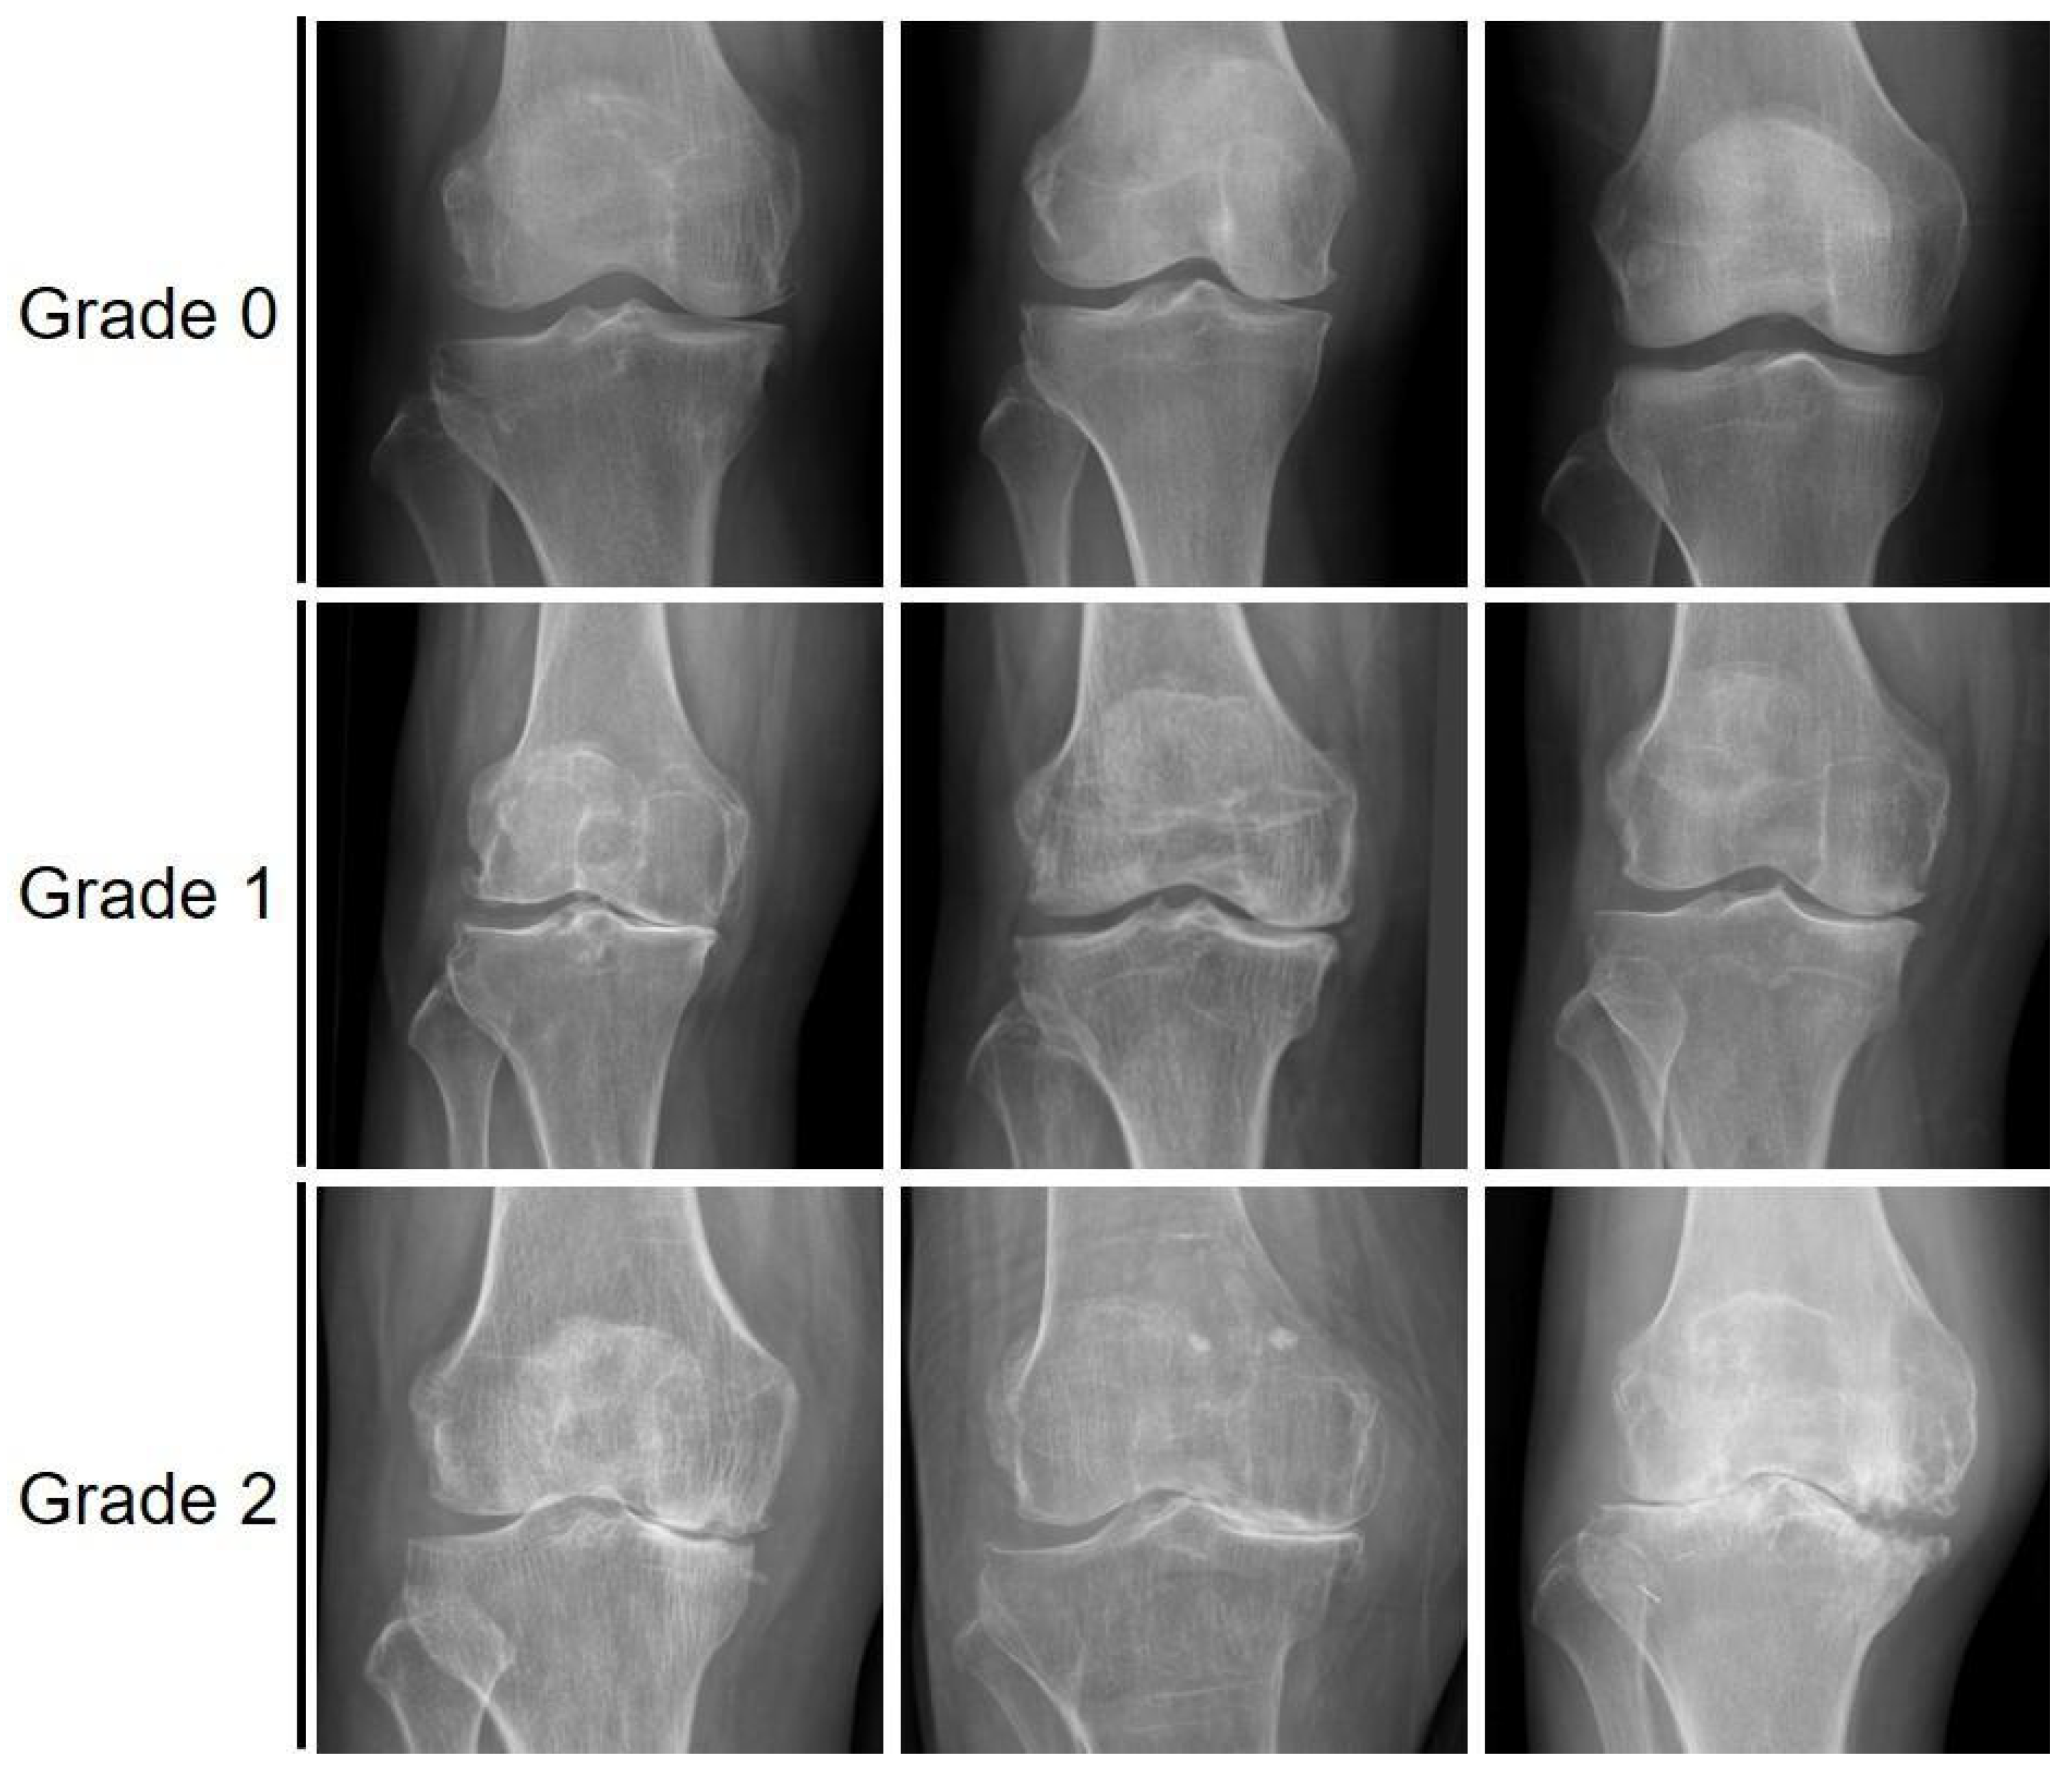

Classification of Grades of Subchondral Sclerosis from Knee Radiographic Images Using Artificial Intelligence

2.1. Data Collection and Labeling